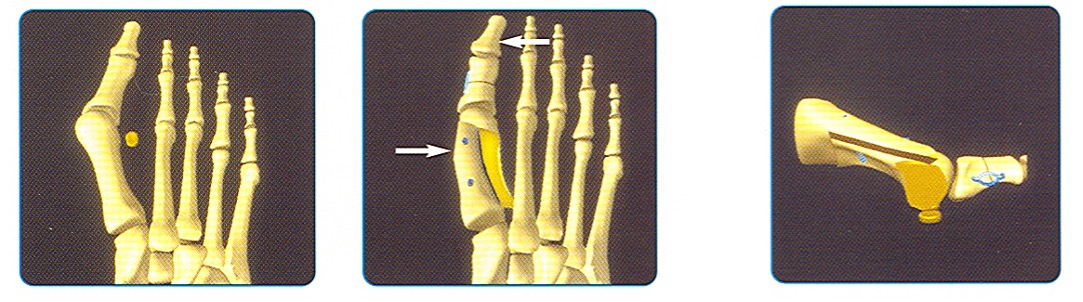

Dafür stehen mehr als eine einzige Methode zur Verfügung. Grundsätzlich haben aber alle dasselbe Ziel: Rückverschieben des Grosszehen-Grundgelenkes an seine angestammte Position. Die von uns in den weitaus meisten Fällen angewandte Methode der Scarf-Osteotomie in den Modifikationen von Barouk und Maestro hat sich dabei hervorragend bewährt und kann in den allermeisten Fällen mit dauerhaftem Erfolg die Korrektur bewirken. Im Prinzip wird dabei der erste Mittelfussknochen (von der Seite gesehen) Z-förmig durchtrennt. Die dabei entstehenden Fragmente werden so gegeneinander verschoben, dass die Achse des ersten Strahls korrigiert werden und dadurch die Sehnen an ihren angestammten Platz zu liegen kommen (oder anders ausgedrückt: das Grundgelenk der ersten Zehe wird zu demjenigen der zweiten Zehe hinbewegt). In dieser Position werden die Knochenteile dann wieder mittels zwei Spezialschrauben fixiert und die überstehenden Knochenteile abgetragen.

Häufig ist es auch zusätzlich notwendig, das ebenfalls verkrümmte Grundglied der Grosszehe zu korrigieren. Dies kann durch Entnahme eines entsprechenden Knochenkeils bewirkt werden. Die Fixation erfolgt hier mit einer Spezialklammer, die eine sofortige Stabilität garantiert.

Schematische Darstellung der Operation